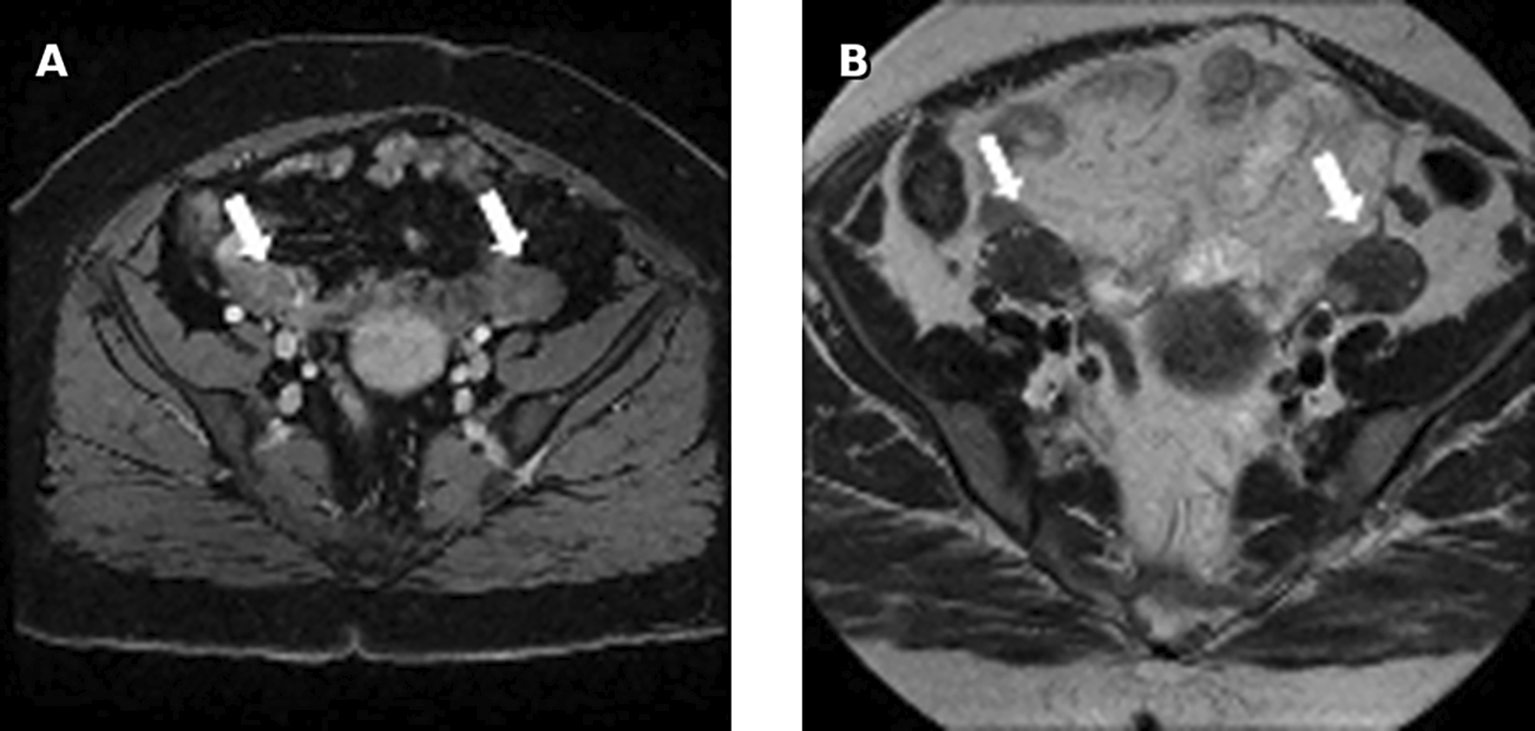

On MRI, bilateral, round solid ovarian masses with homogenous low signal intensity on T2 were found. These masses were classified as ORADS category 2. No adrenal mass was noted ( Figure 3).

Pelvic ultrasound showed an enlarged uterus and right ovary (measured at 60*30 mm). MRI revealed an enlarged right ovary, with several follicles as well as a solid mass with intermediate signal on T2 and avid enhancement after gadolinium administration. The left ovary was of normal size 26*24 mm. No mass was found ( Figure 7).

Testosteronemia was at 9.22 nmol/l with normal levels of SDHEA (873 ng/ml). Lab tests revealed a normal basic cortisol level with no findings suggestive of cushing’s syndrome. A Thoraco-abdominopelvic CT was performed showing a 30mm right adrenal mass with spontaneous density at 7 HU and an absolute wash out at 35% suggestive of an adenoma. Pelvic MRI revealed a solid left ovarian mass with heterogeneous signal on T2 with an intermediate risk time intensity curve (B) on dynamic contrast enhancement, classified as ORADS category 4 ( Figure 12).